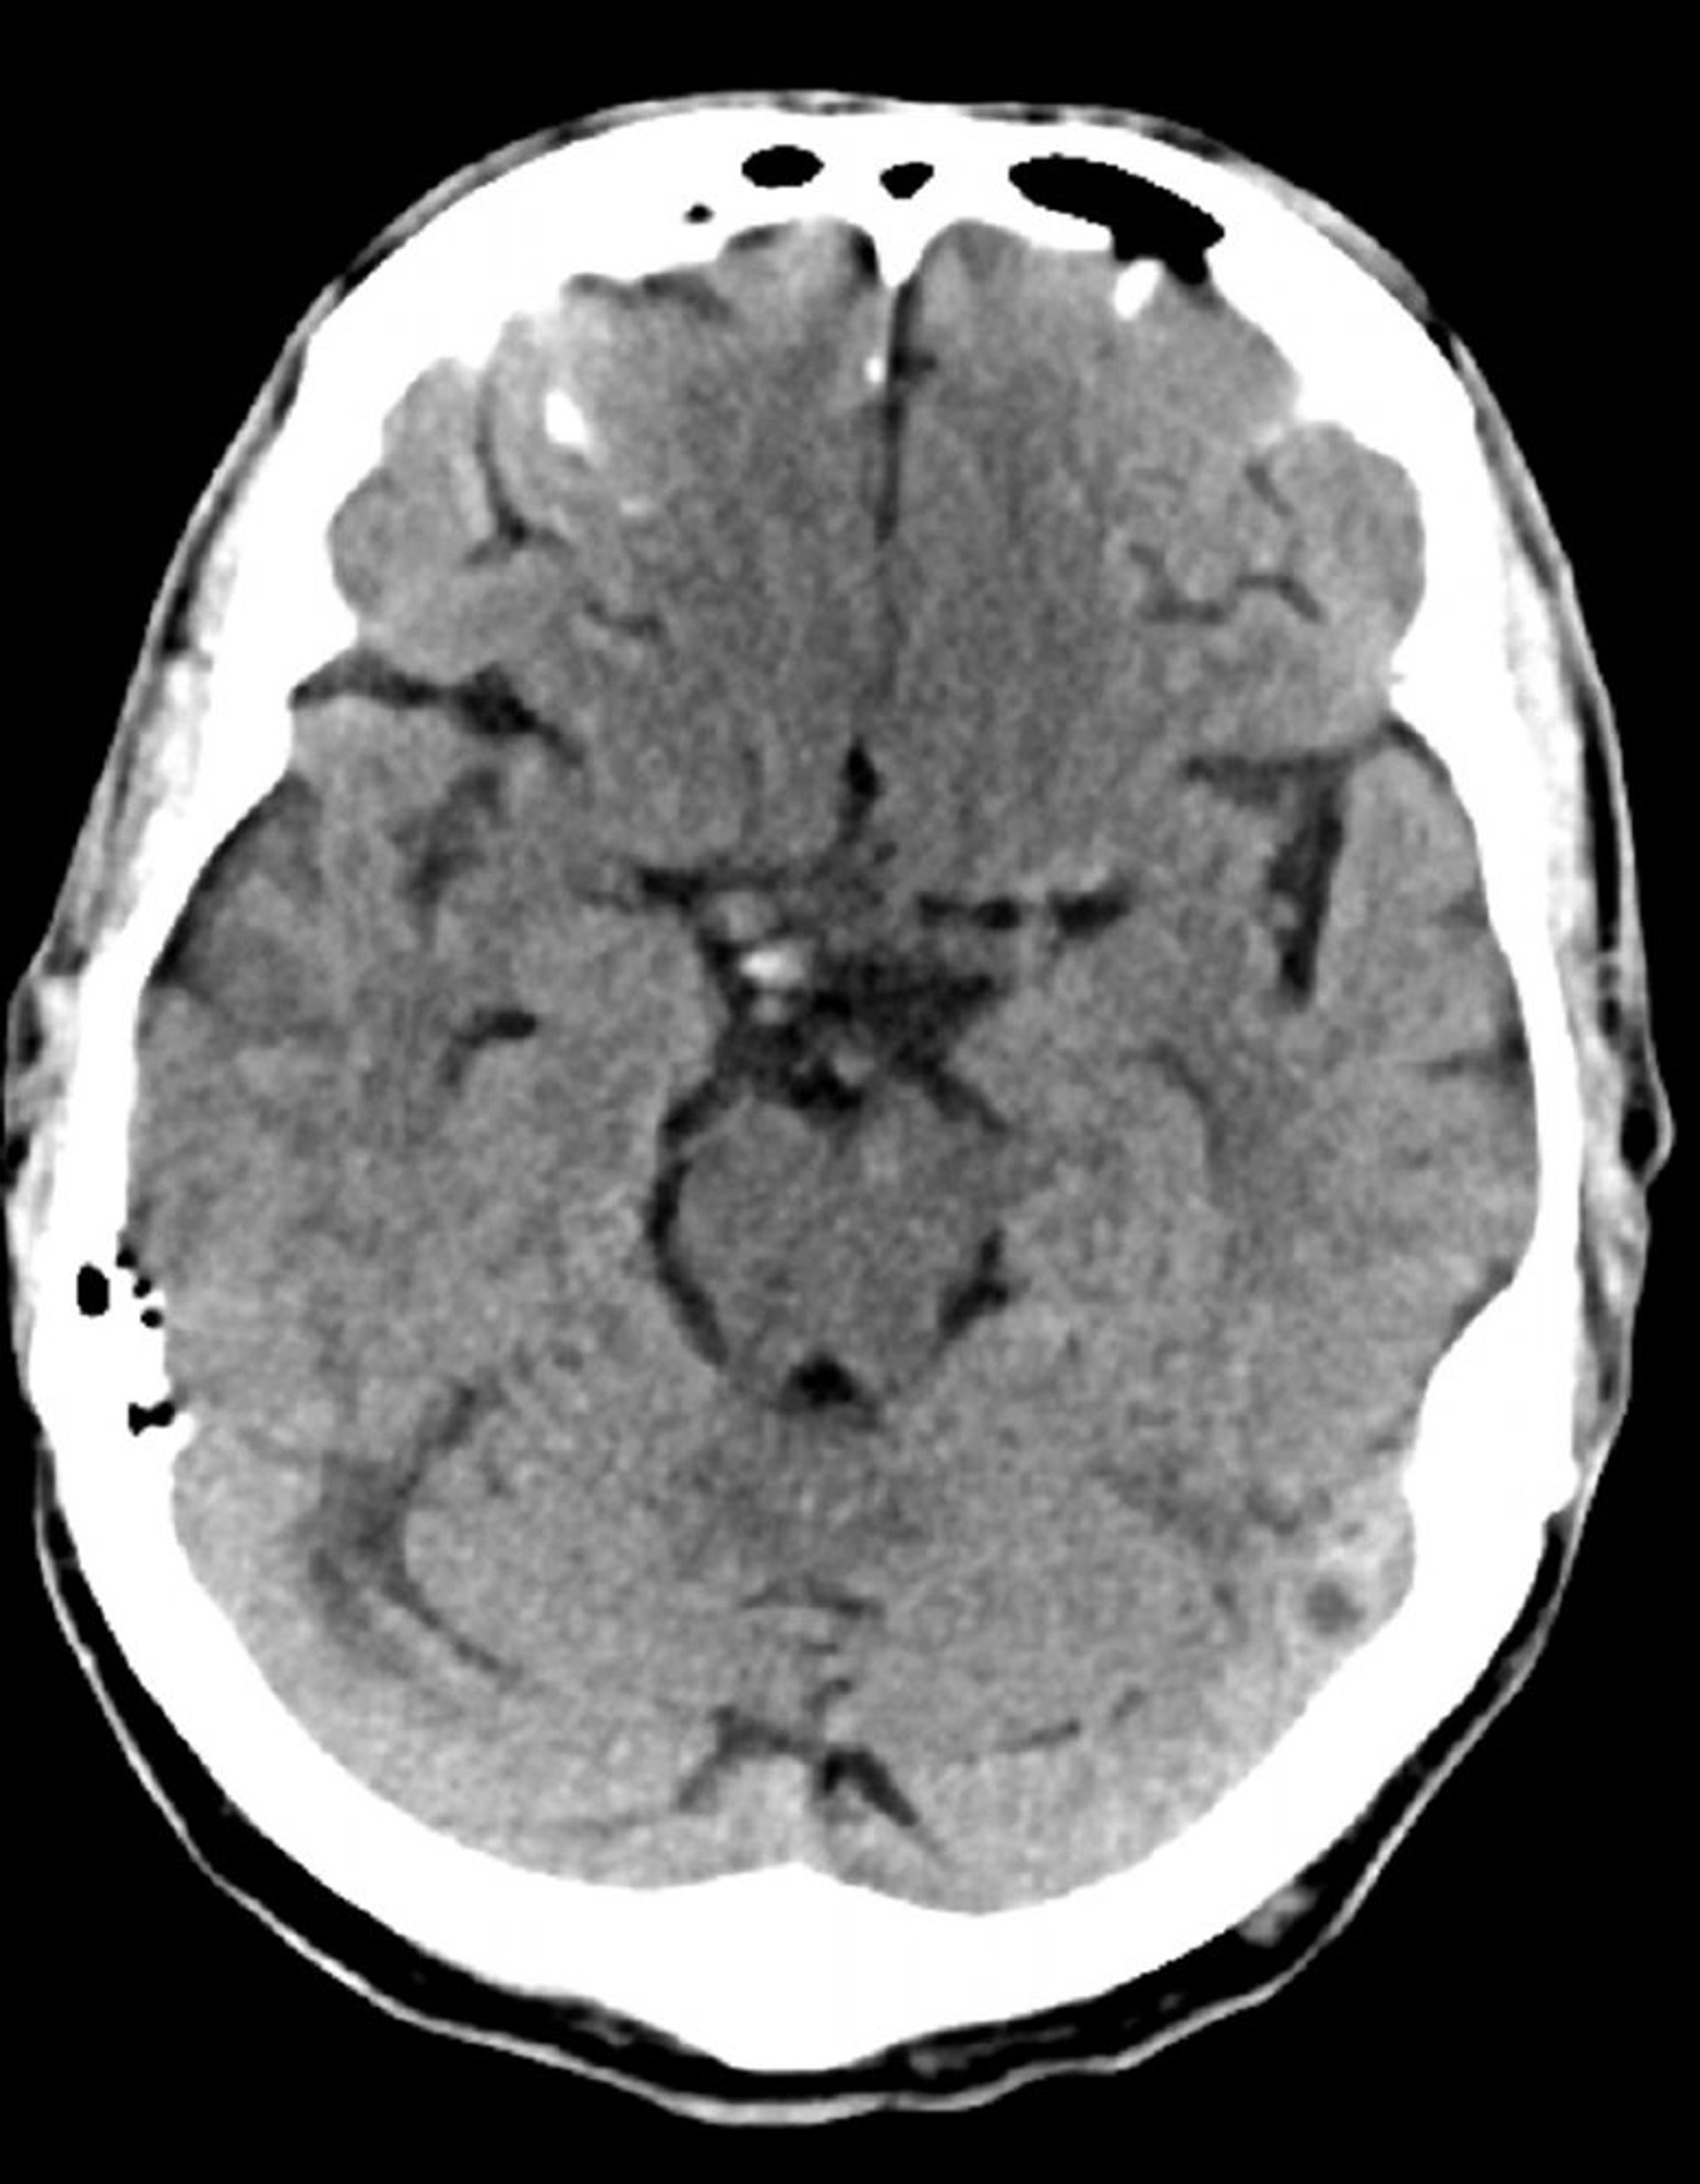

Normal Head CT Scan (Adult, Age 74) – Slide 7

This image is a normal CT scan of the head of an adult aged 74. When compared with the normal CT scan of the head of a 30-year-old, the ventricles and sulci are larger. These findings are normal in this age group.